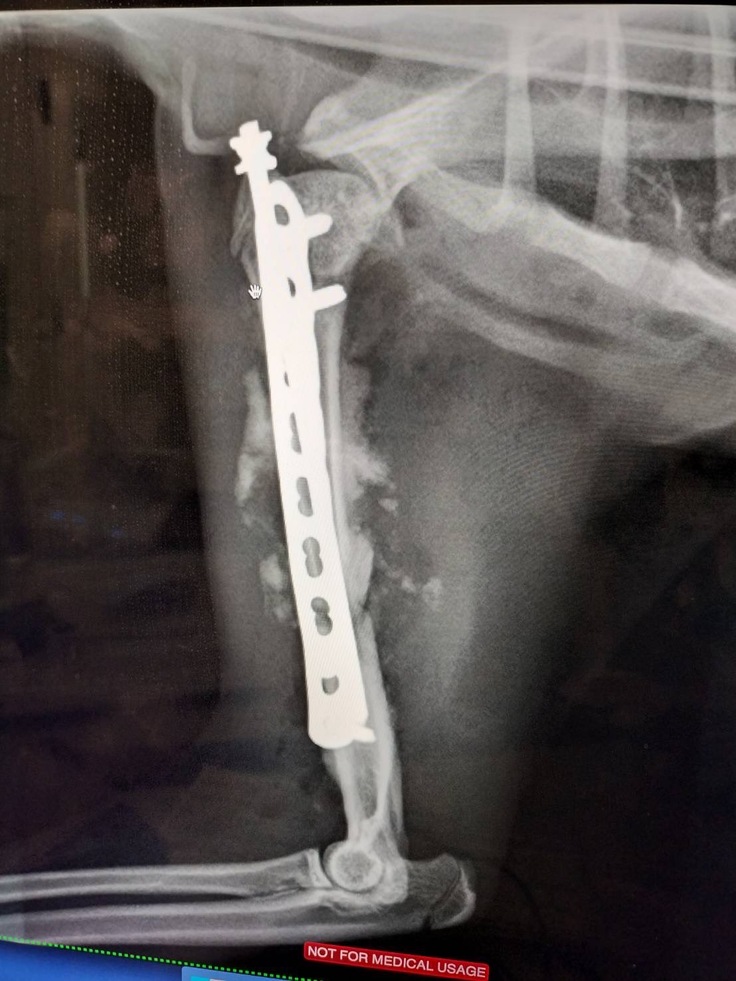

手術で修復したことがわかるレントゲン

ちょっと手の先に麻痺が残りました